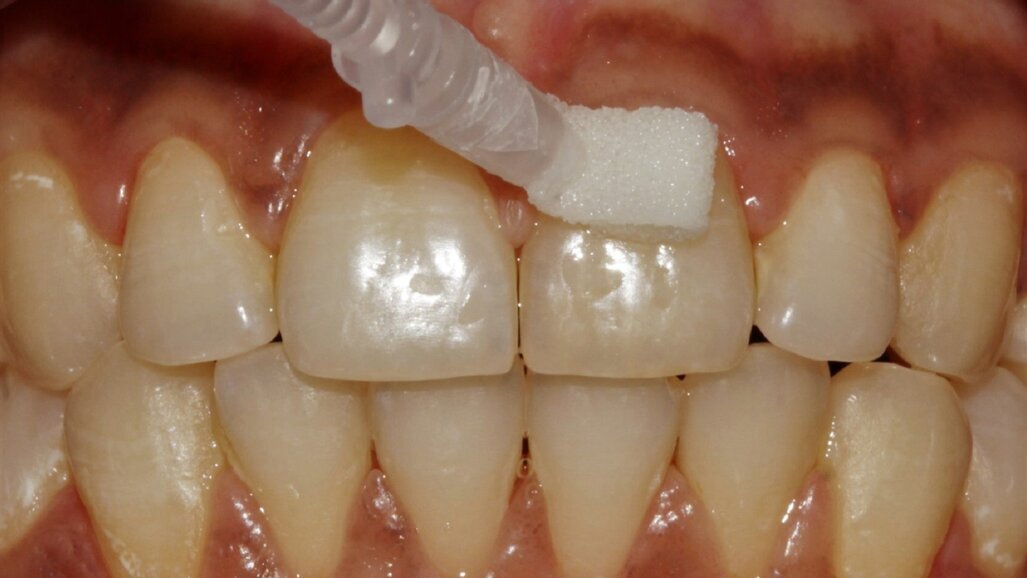

tooth in need of curodont

Curodont application

Curodont is applied directly to that early area. The treatment seeps into the microscopic pores of the enamel and creates a framework that attracts minerals like calcium and phosphate.

Over time, this process helps restore the strength and integrity of the enamel, stopping the progression of decay.